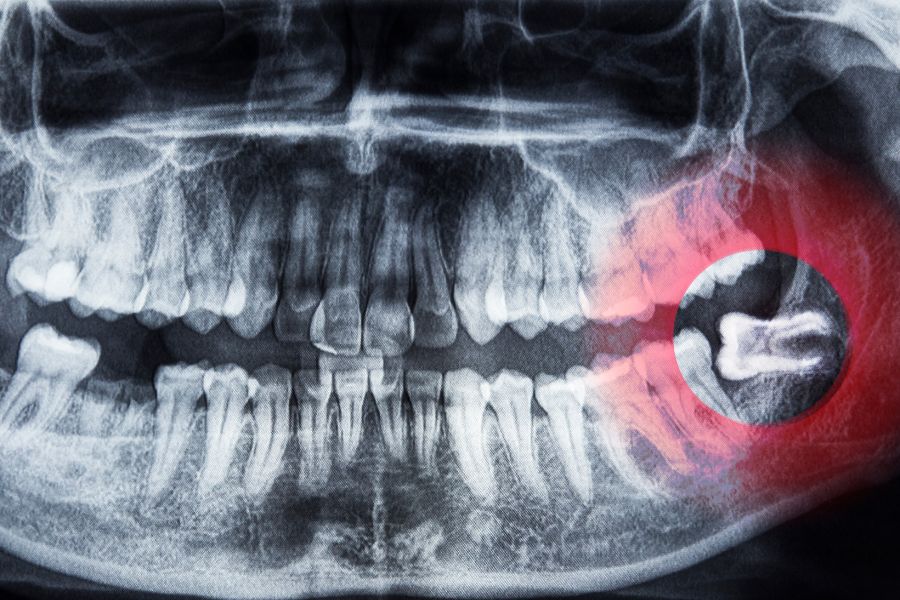

- Bước 1: Thăm khám và chụp X-quang

Bác sĩ kiểm tra tổng quát sức khỏe răng miệng và chụp phim X-quang để đánh giá vị trí, chiều hướng mọc. Bác sĩ xác định mức độ phức tạp của răng và chuẩn bị kế hoạch tiểu phẫu phù hợp.